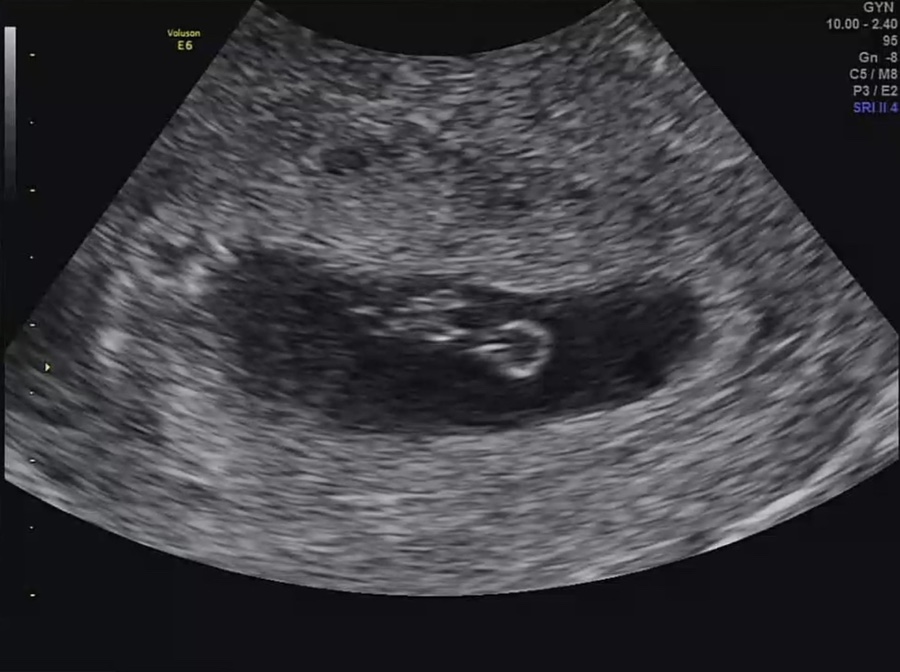

임신 7주 2일 심장 소리를 듣는다!

일단 저번보다 아기가 많이 컸다고 비춰주셨어요 아기의 크기는 1.1cm, 7주, 1일 정도로 예상 주수에 맞게 커진다고 합니다.

심장 소리도 듣고 왔습니다. ㅎㅎ 132bpm 아주 힘차요 ㅎㅎ

오른쪽 동그란 거 노른자 같아?동그란 반지 모양 잘 나왔어요 ㅋㅋ

그리고 빛나는 게 아기키라키라 하는 걸 보여줬어요 (웃음)